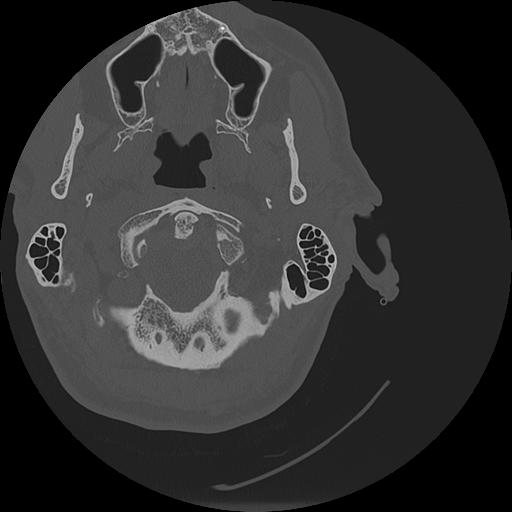

7 HUESO,,Vol,0.5,HUESO,,